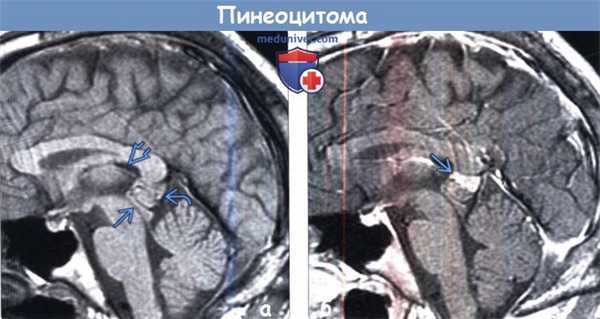

(а) На рисунке сагиттального среза изображены кистозное объемное образование эпифиза с уровнем раздела жидкость-жидкость и узловой компонент опухоли, расположенный по периферии образования, что характерно для пинеоцитомы. Значимый масс-эффект отсутствует. Питуицитомы могут являться случайными находками или выявляться при гидроцефалии.

(б) Бесконтрастная КТ, аксиальный срез: определяется классический пример пинеоцитомы. Обратите внимание на периферические кальцификаты «взрывного» характера в структуре этого мелкого образования, произрастающего из пинеальной области. Размеры опухоли едва превышают 1 см. Гидроцефалия отсутствует.

(а) МРТ, Т1-ВИ, сагиттальный срез: определяется объемное образование с четкими границами, расположенное в пинеальной области и изоинтенсивное по отношению к паренхиме мозга. Образование оказывает умеренный масс-эффектна тектум, однако сильвиев водопровод интактен, а гидроцефалия отсутствует. Пинеальная опухоль располагается под внутренними мозговыми венами и валиком мозолистого тела.

(б) МРТ, постконтрастное Т1-ВИ, сагиттальный срез: у того же пациента определяется гетерогенный характер контрастирования пинеоцитомы с его наибольшей выраженностью в области верхнего узлового компонента.